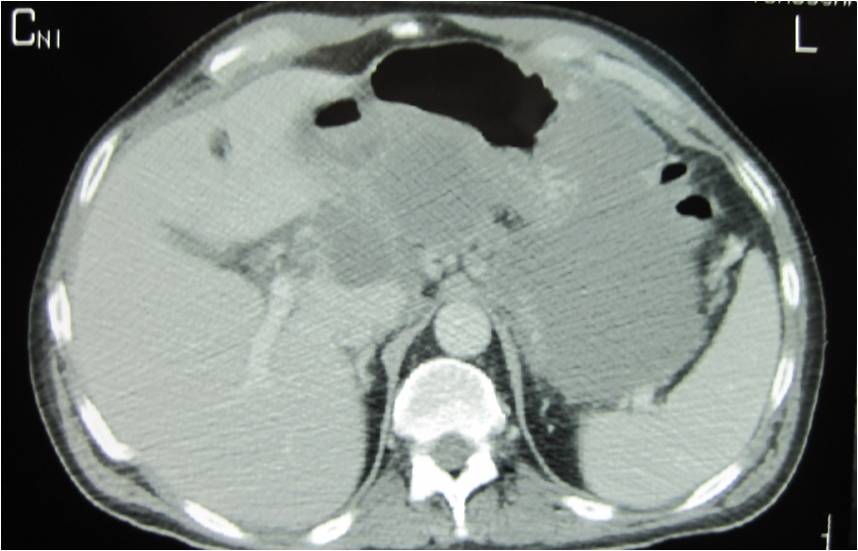

- Large abdominal abscess post- pancreatic surgery

- Successful drainage